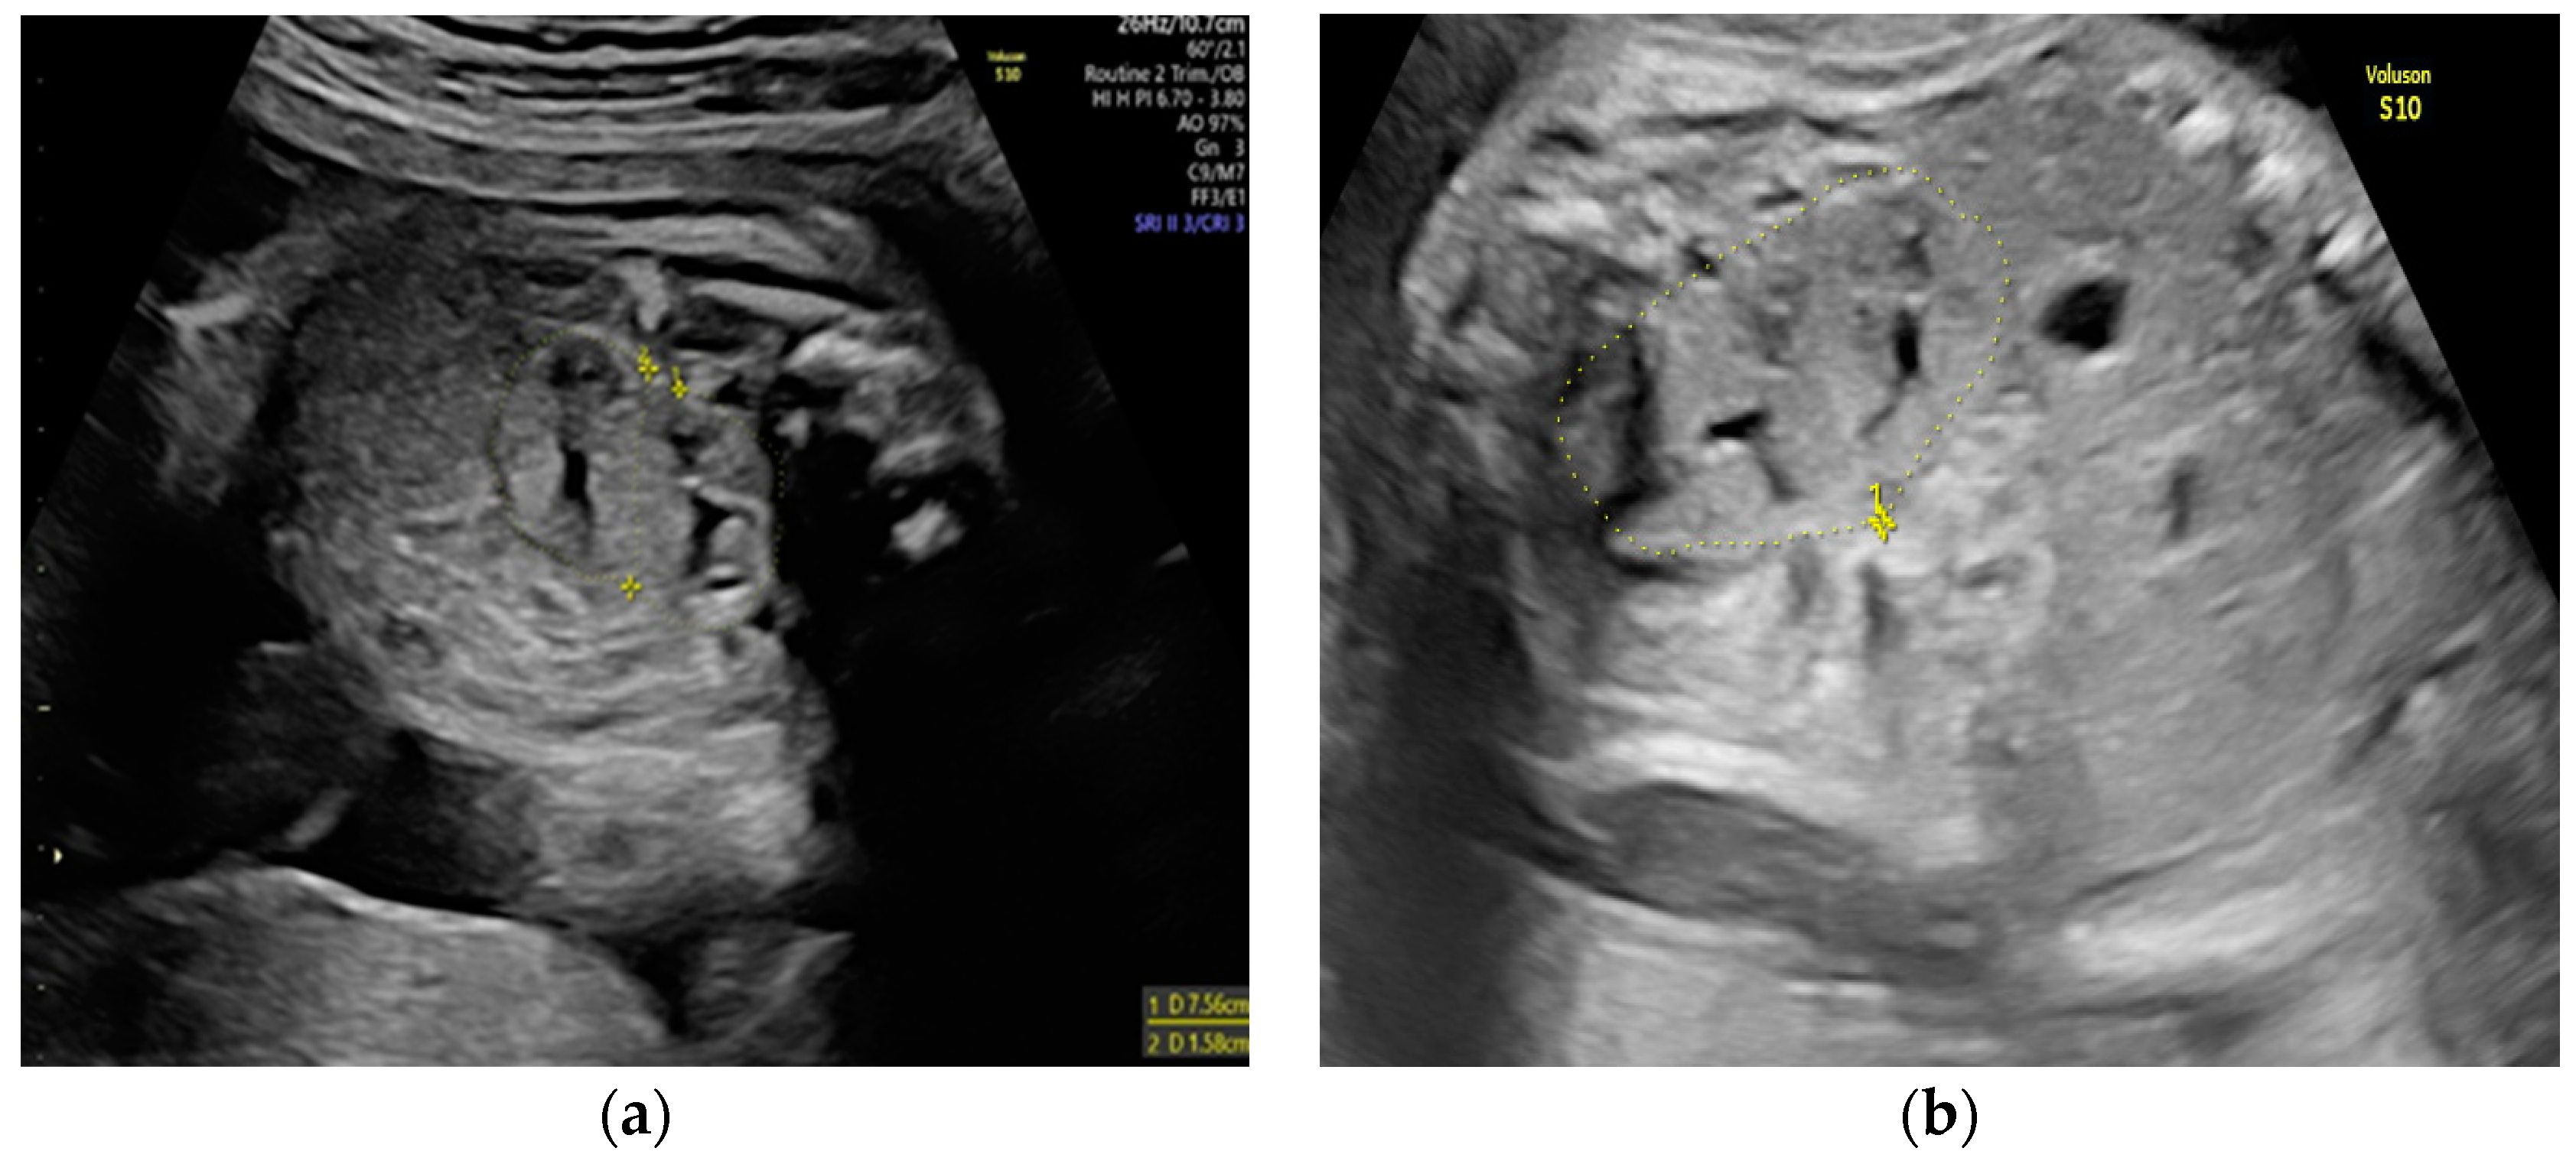

She returned at 20 weeks and 4 days for the second-trimester anomaly scan. Our careful ultrasound examination revealed bilateral empty renal fossa, a normal bladder, and normal amniotic fluid volume. No other fetal anomalies were detected, and the fetus was normally grown. Renal tissue was found in the fetal pelvis, close to the bladder and to the right (Figure 1). On a transvaginal scan, we demonstrated a duplex kidney with two renal pelvises (Figure 2a,b). The artery supply was seen coming from the internal iliac artery (Figure 3a,b). We offered invasive testing, but the patient declined. A fetal echocardiography was also performed, which showed no abnormalities of the fetal heart.

Figure 1. Pelvic kidney (the renal tissue is in the fetal pelvis, close to the bladder and to the right).